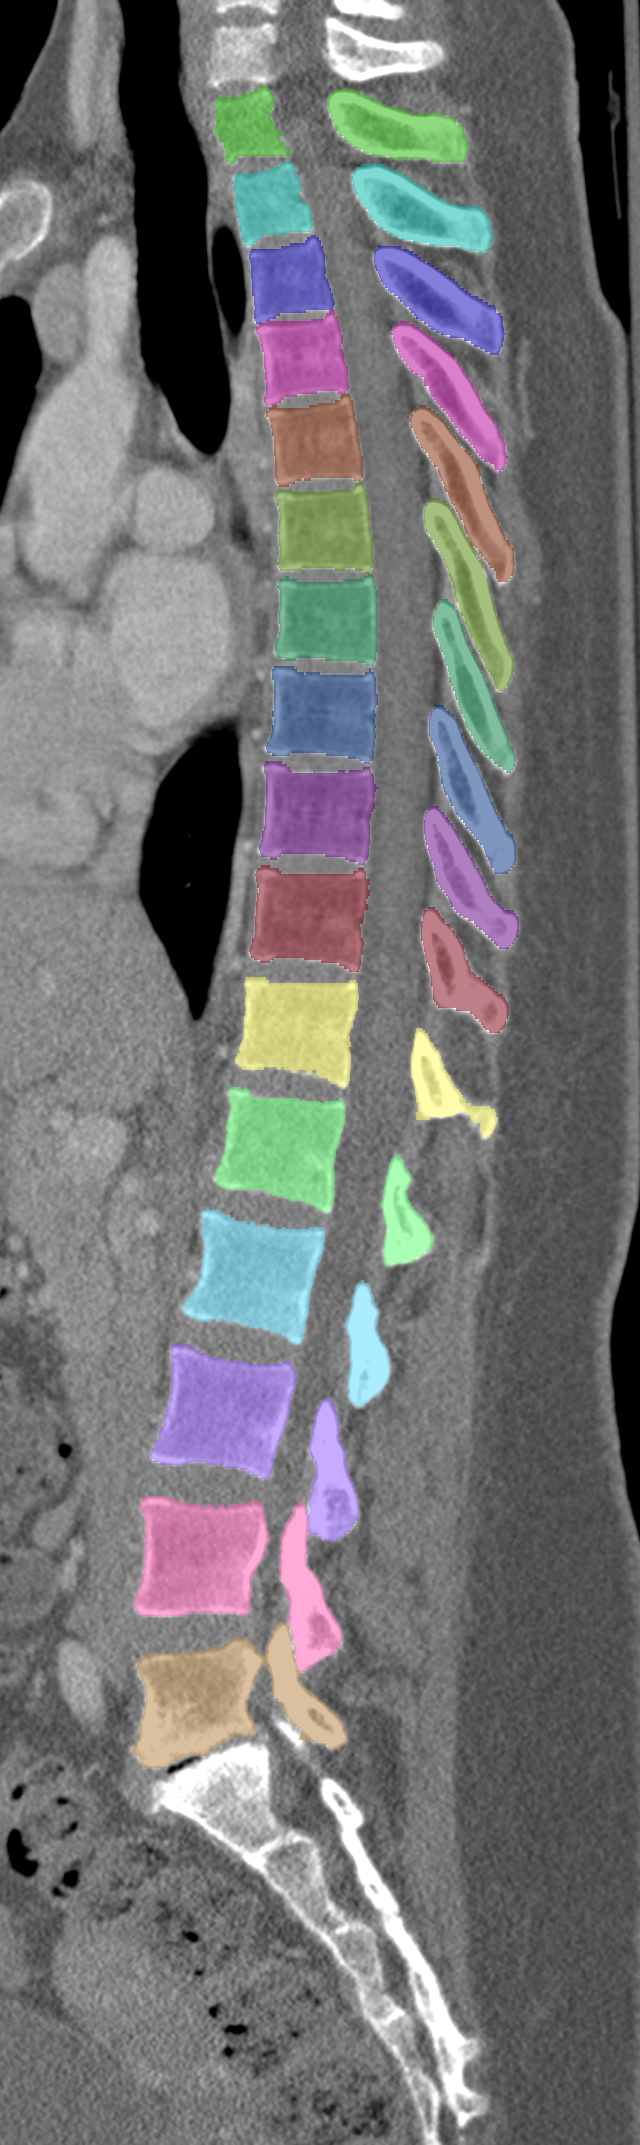

Normalized CT images and reference segmentations of thoracic and lumbar vertebrae from the CSI 2014 workshop

This is the dataset of the vertebra segmentation challenge of the CSI 2014 workshop that was held in conjunction with MICCAI 2014.

The data that is published here has been normalized:

- Voxel values are Hounsfield values and have been clipped to [-1000, 3095]

- Vertebrae have been anatomically labeled (8 = T1, 9 = T2, ..., 24 = L5)

- Because not always all visible vertebrae were segmented in the original data, only segmentations of the thoracic and lumbar vertebrae have been retained